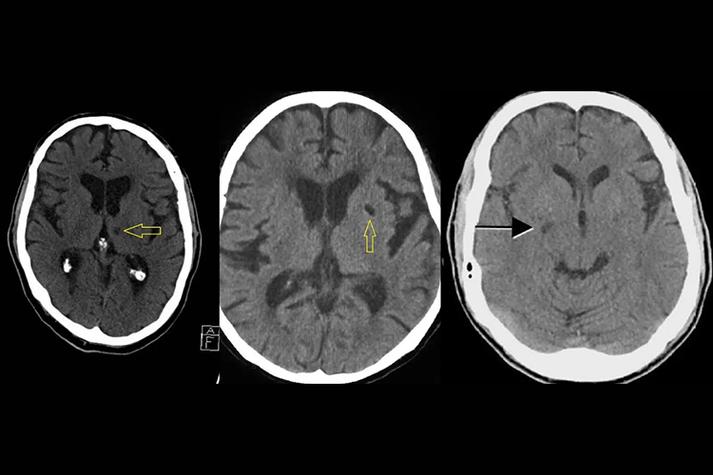

如何“看”一张脑CT片子(非专业人士视角)

想象一下,你拿着一张CT胶片或电脑屏幕上的图像,从上到下、从左到右地观察。

(图片来源网络,侵删)

第一步:看整体,排除大问题

- 中线结构: 观察颅骨中央的线状结构(大脑镰)和两侧脑室之间的结构,如果这条线明显地向一侧偏移,说明一侧大脑肿胀严重,是颅内压增高的紧急信号,需要立即处理。

- 脑沟回: 对比左右两侧大脑表面的沟回,如果某一侧的脑沟变浅、变平甚至消失,而另一侧正常,提示该侧大脑存在水肿或肿胀。

- 脑室系统: 观察两侧侧脑室是否对称,如果一侧脑室被挤压变小,另一侧被牵拉变大,也是占位效应的表现。

第二步:分区对比,寻找异常

- 看什么: 仔细对比左右两侧的基底节区(豆状核)和岛叶(大脑外侧深部的一个三角形结构),如果发现一侧的这些区域密度变低(变黑),或者边界变得模糊不清,高度怀疑大脑中动脉供血区梗死。